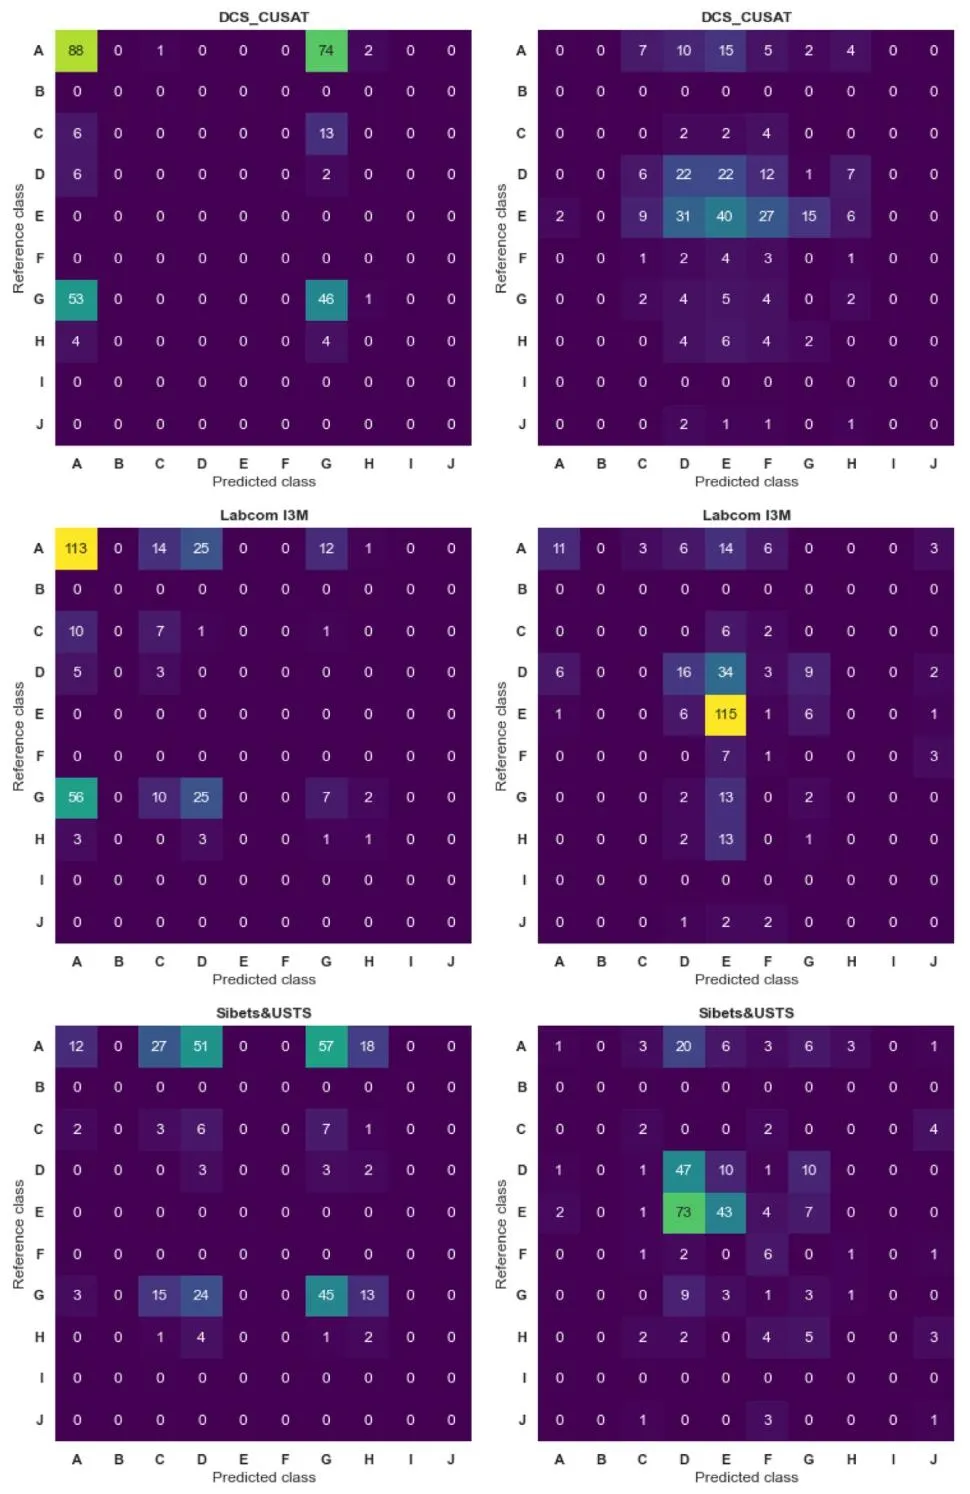

Fig. A.2. Confusion matrices of the results per team (DCS_CUSAT, Labcom I3M, and Sibets&USTS**) for anterior (left column) and posterior (right column) classification. Rowsrepresent reference classes, while columns represent predicted classes. Values in each cell indicate the count of instances classified accordingly

图A.2. 各团队(DCS_CUSAT、Labcom I3M及Sibets&USTS)在Willis环前部(左列)和后部(右列)分类中的混淆矩阵结果** 行代表参考类别(真实类别),列代表预测类别。每个单元格中的数值表示被分到相应类别的样本数量。